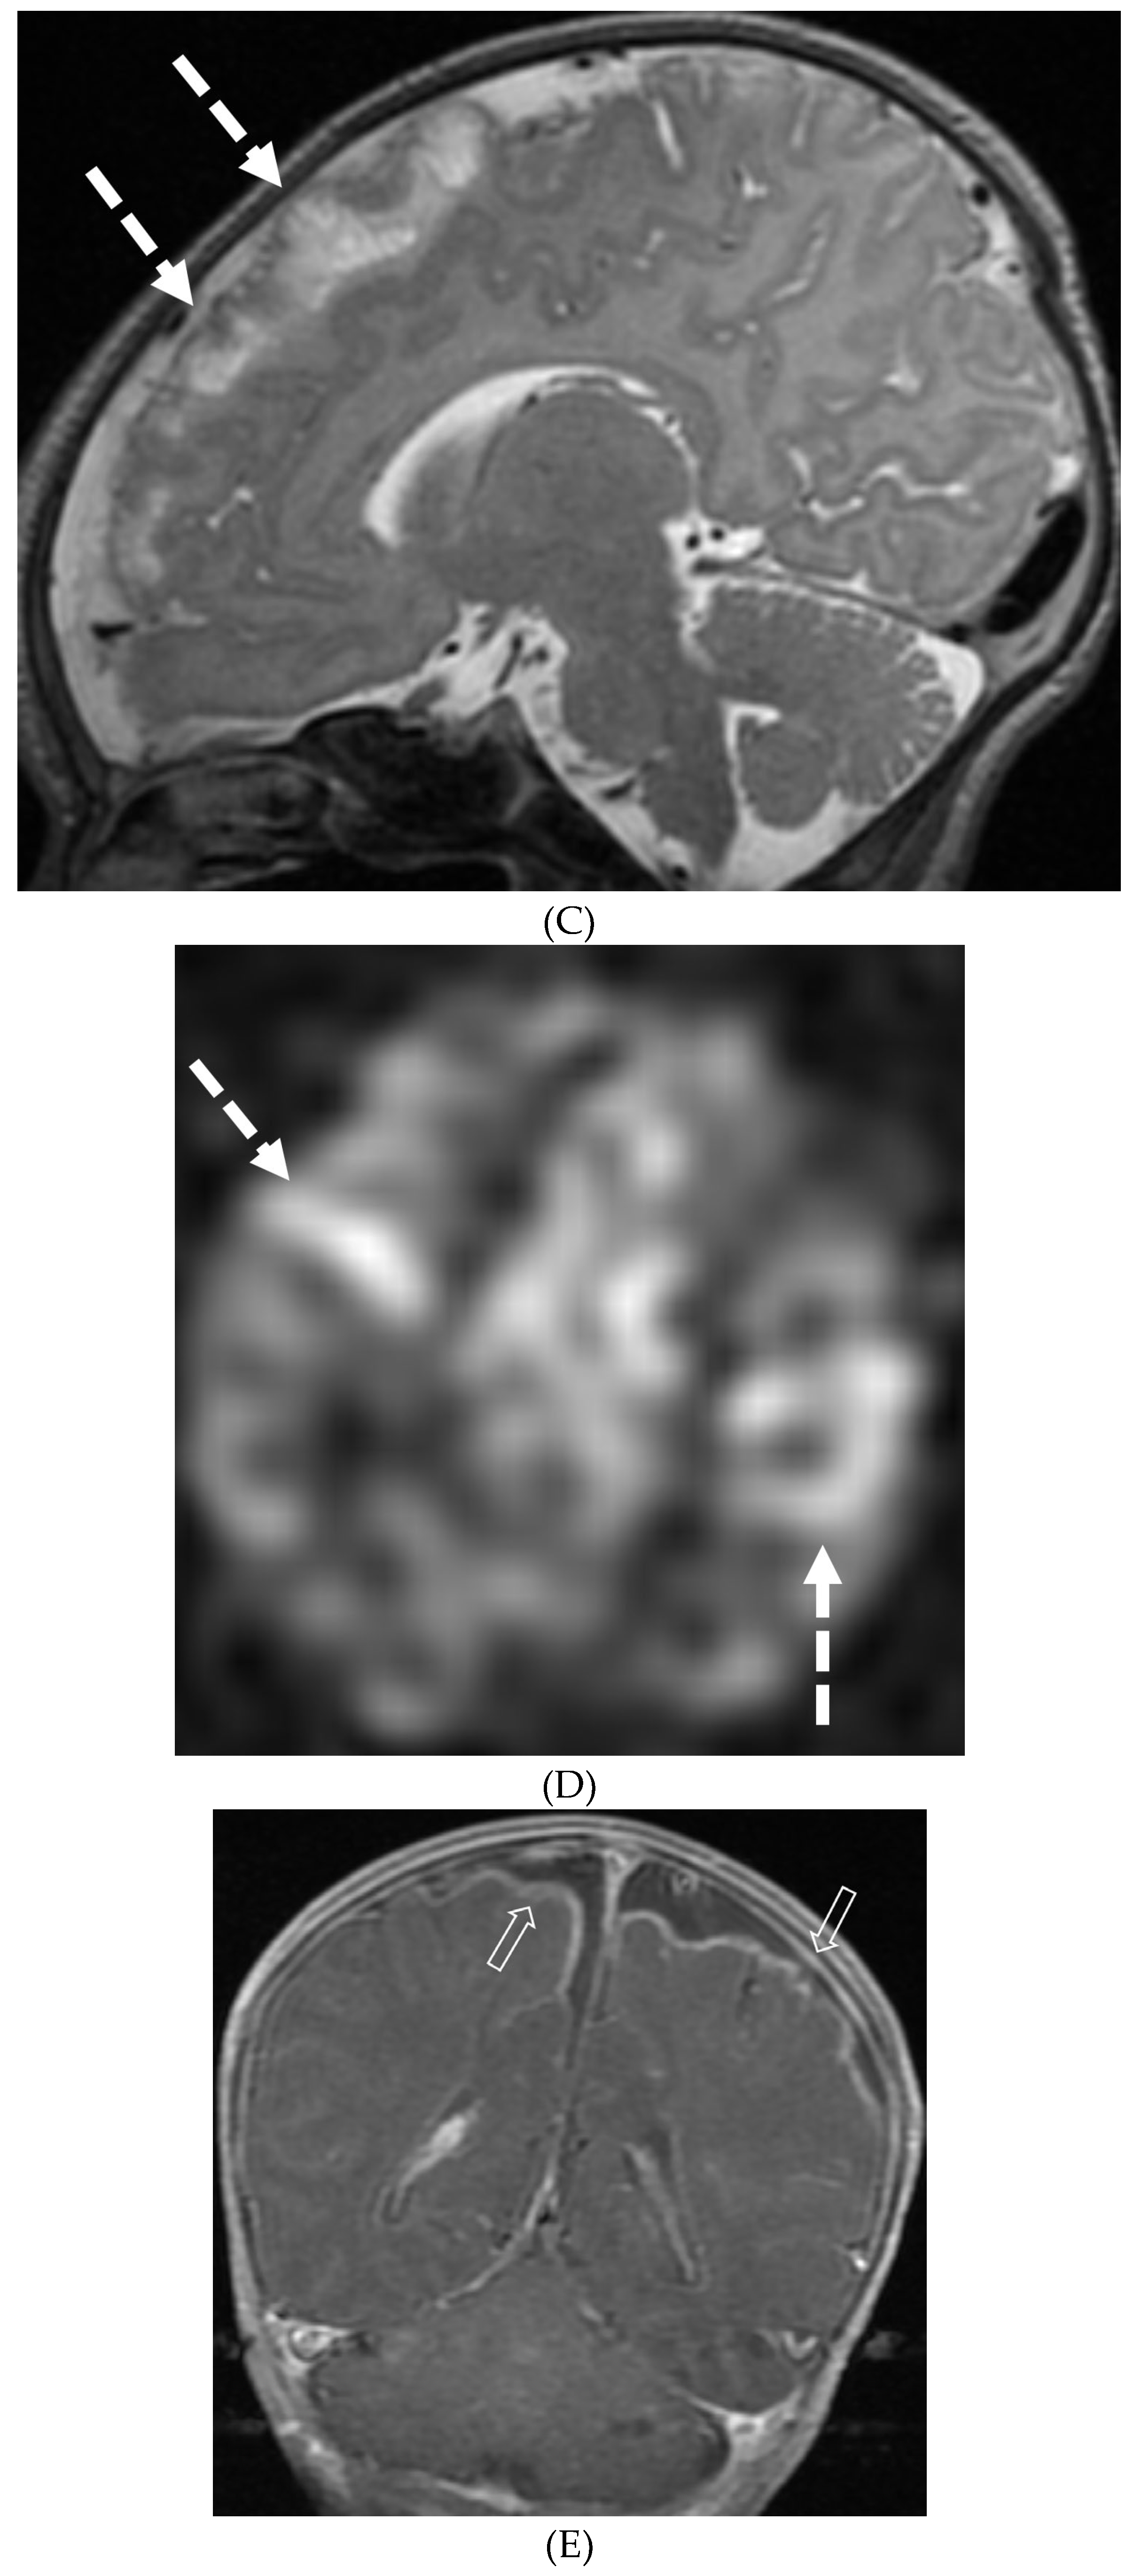

- Li L, Liu W, Cai Q, Liu Y, Hu W, Zuo Z, Ma Q, He S, Jin K. Leptomeningeal enhancement of myelin oligodendrocyte glycoprotein antibody-associated encephalitis: uncovering novel markers on contrast-enhanced fluid-attenuated inversion recovery images. Front Immunol. 2023 Jun 20;14:1152235. PMID: 37409120; PMCID: PMC10318903. [CrossRef]

- Shahriari M, Sotirchos ES, Newsome SD, Yousem DM. MOGAD: How It Differs From and Resembles Other Neuroinflammatory Disorders. AJR Am J Roentgenol. 2021 Apr;216(4):1031-1039. Epub 2021 Feb 17. PMID: 32755221. [CrossRef]

- Gadde JA, Wolf DS, Keller S, Gombolay GY. Rate of Leptomeningeal Enhancement in Pediatric Myelin Oligodendrocyte Glycoprotein Antibody-Associated Encephalomyelitis. J Child Neurol. 2021 Oct;36(11):1042-1046. PMID: 34547933; PMCID: PMC9054459. [CrossRef]

- Valencia-Sanchez C, Guo Y, Krecke KN et al. Cerebral Cortical Encephalitis in Myelin Oligodendrocyte Glycoprotein Antibody-Associated Disease. Ann Neurol. 2023 Feb;93(2):297-302. Epub 2022 Dec 2. PMID: 36372941; PMCID: PMC10107670. [CrossRef]